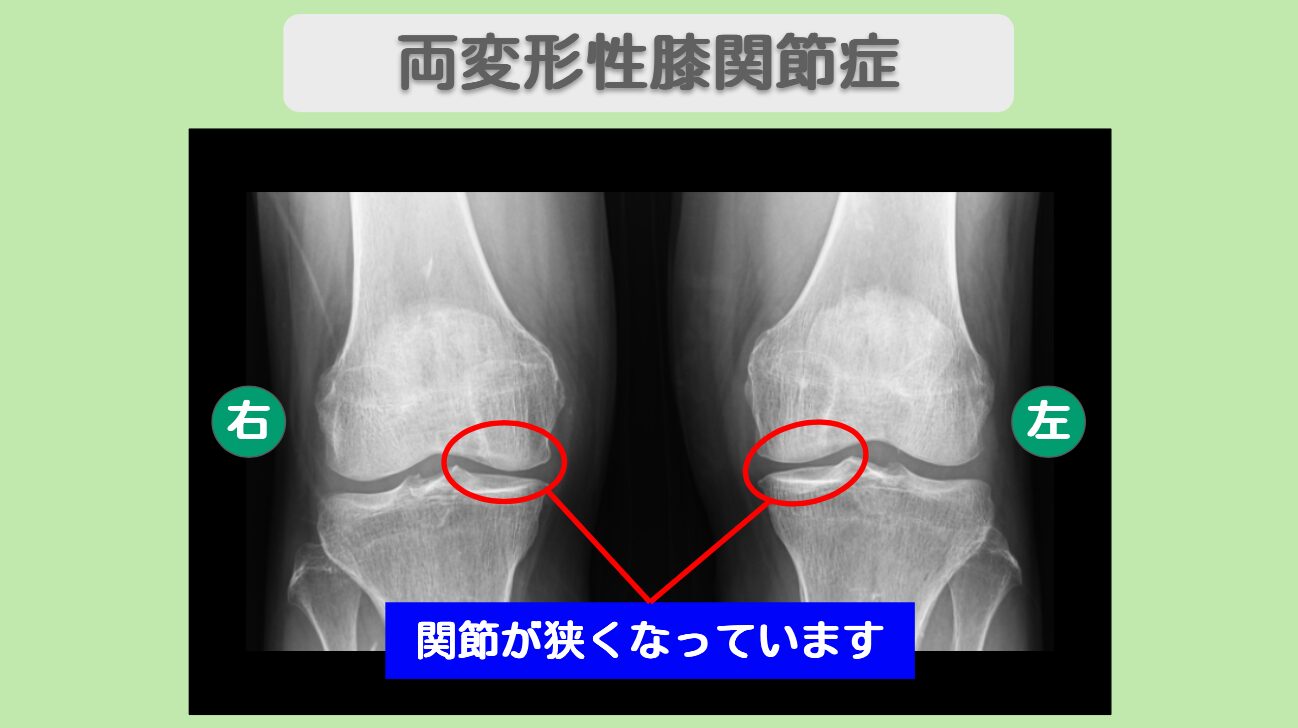

MRI・レントゲン所見

MRIにてヘルニアと狭窄を認めます。

整形外科で腰椎椎間板ヘルニアと中期の両膝変形性関節症と診断され、症状の悪化により手術を決断されていました。しかし手術への不安もあり、他の選択肢を探していらっしゃいました。